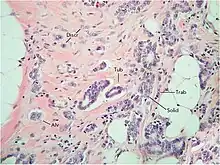

Despite the considerable structural diversity of the primary breast tumor, five main types of morphological structures can be distinguished: alveolar, trabecular, tubular and solid structures, and discrete groups of tumor cells (Fig. 2). The alveolar structures are tumor cell clusters of round or slightly irregular shape. The morphology of the cells that form this type of structures varies from small cells with moderate cytoplasm and round nuclei to large cells with hyperchromatic nuclei of irregular shape and moderate cytoplasm. The trabecular structures are either short, linear associations formed by a single row of small, rather monomorphic cells or wide cell clusters consisting of two rows of medium-sized cells with moderate cytoplasm and round normochromic or hyperchromatic nuclei. The tubular structures are formed by a single or two rows of rather monomorphic cells with round normochromic nuclei. The solid structures are fields of various sizes and shapes, consisting of either small cells with moderate cytoplasm and monomorphic nuclei or large cells with abundant cytoplasm and polymorphic nuclei. Discrete groups of cells occur in the form of clusters of one to four cells with variable morphologies.[2]

According to the data accumulated to date, it may be assumed that different morphological structures of breast tumors correspond to certain types of invasion. Therefore, alveolar, trabecular, and solid structures that are characterized by the presence of cell-cell contacts may be referred to morphological manifestations of collective migration, while discrete groups of tumor cells may be referred to manifestations of individual migration. Interestingly, the first batch of data obtained in a study of the expression of cell adhesion genes fully confirms this hypothesis. For example, there was a decrease in the activity of the genes of cadherins, which are responsible for cell-cell contacts, in the order: solid – alveolar and trabecular structures – discrete groups of tumor cells. In this case, the number of expressed genes of integrins involved in the adhesion of tumor cells to the extracellular matrix was reduced in the order: solid and alveolar – trabecular structures – discrete groups of tumor cells.[2]